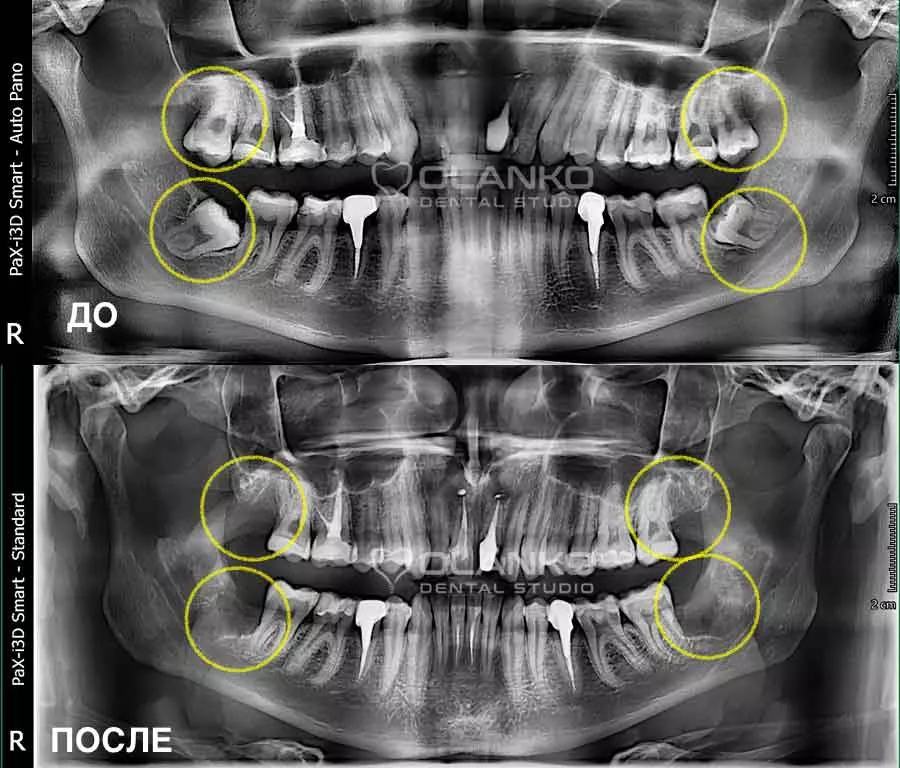

Фото панорамний знімок зубів ДО і ПІСЛЯ видалення чотирьох зубів мудрості

Фото панорамний знімок зубів ДО і ПІСЛЯ видалення чотирьох зубів мудрості Оланко Бровари Київ